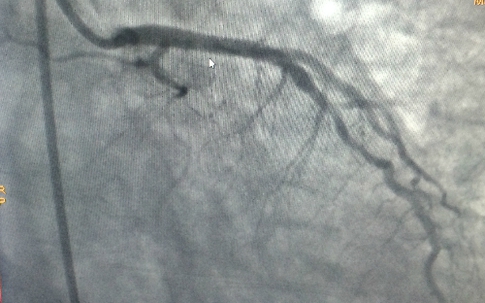

Thanh niên cũng có thể bị đột quỵ não

Y tế

GiadinhNet - Ở Việt Nam, đột quỵ ngày càng có xu hướng trẻ hóa ở cả nam và nữ, ở độ tuổi dưới 30 thậm chí có cả sinh viên.